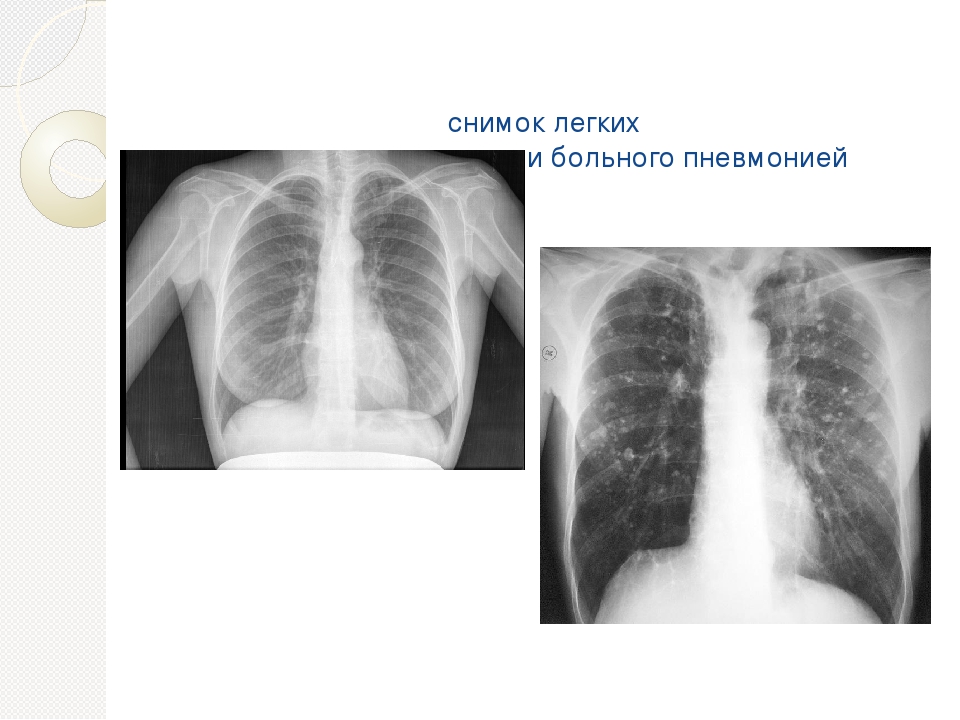

Нормальная рентгенограмма легких: что нужно знать

Раздел: Мудрость в объективе